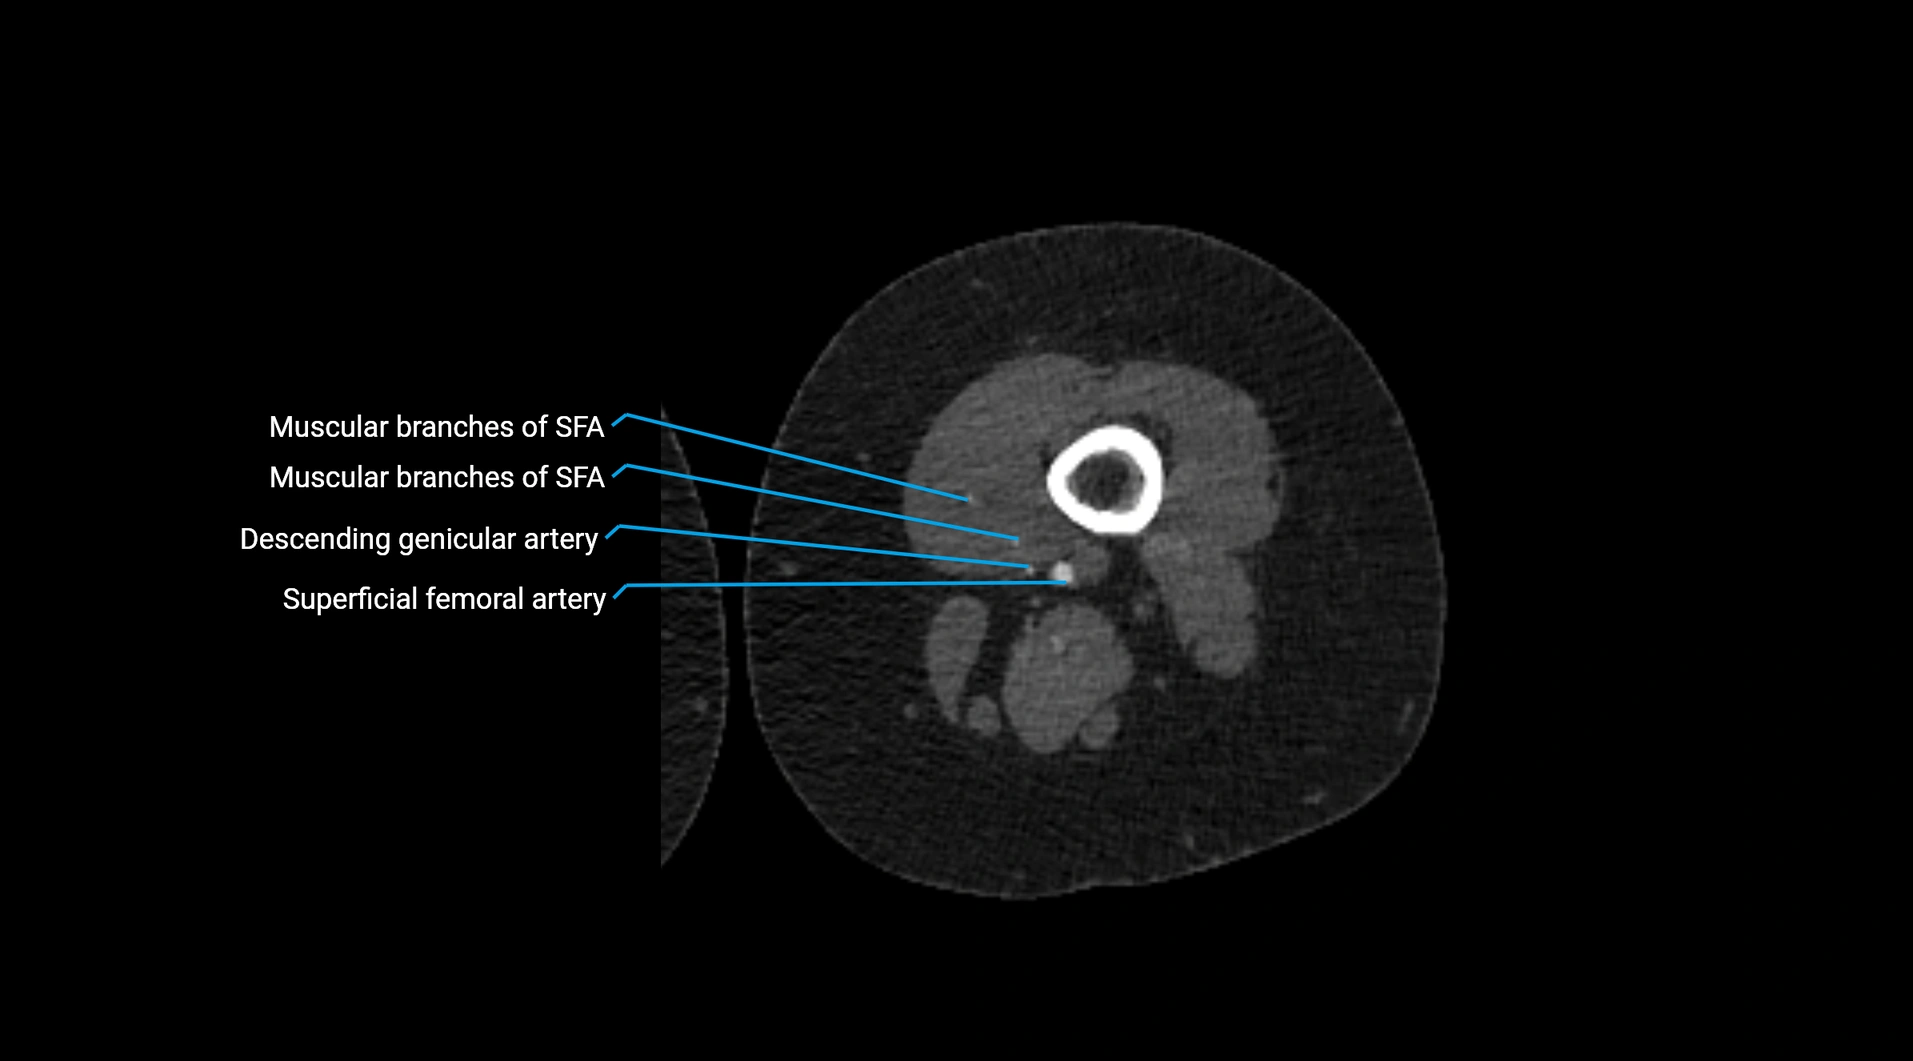

Contrast-enhanced CT (CTA):

• Gold standard for abdominal aortic imaging

• Provides excellent detail of lumen, wall, aneurysm, thrombus, and branch vessels

• Multiplanar and 3D reconstructions help in aneurysm measurement, stent graft planning, and dissection evaluation

• Detects acute rupture, traumatic injury, or occlusion with high sensitivity